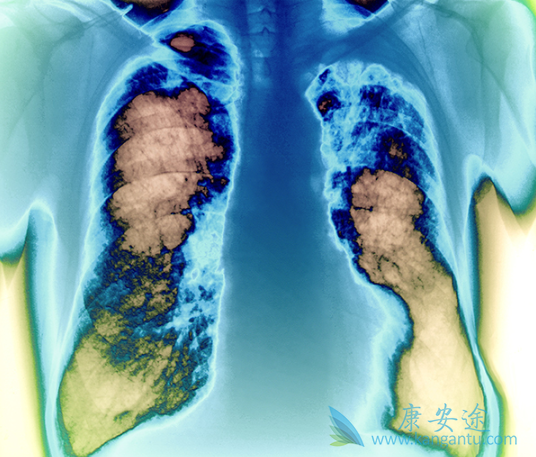

间皮瘤作为一种隐匿性肿瘤,可发于胸膜腔、腹膜腔、睾丸鞘膜或心包的间皮表面,其中大部分病例源于胸膜。恶性胸膜间皮瘤(MPM)是最常见的恶性间皮瘤,绝大多数MPM患者发病年龄在60岁及以上,石棉暴露是发生胸膜间皮瘤最重要的危险因素。大部分患者因逐渐出现非特异性症状而就诊,如胸痛、呼吸困难、咳嗽、声音嘶哑、盗汗或吞咽困难等。正因为MPM的临床表现没有特异性而且隐匿,许多患者在就诊时已偏晚期,使得治疗比较棘手。对于怀疑MPM的患者首选胸部增强CT检查,以确定胸膜异常和病变程度,如果存在胸腔积液,可以进行胸水细胞学病理诊断或胸膜活检。